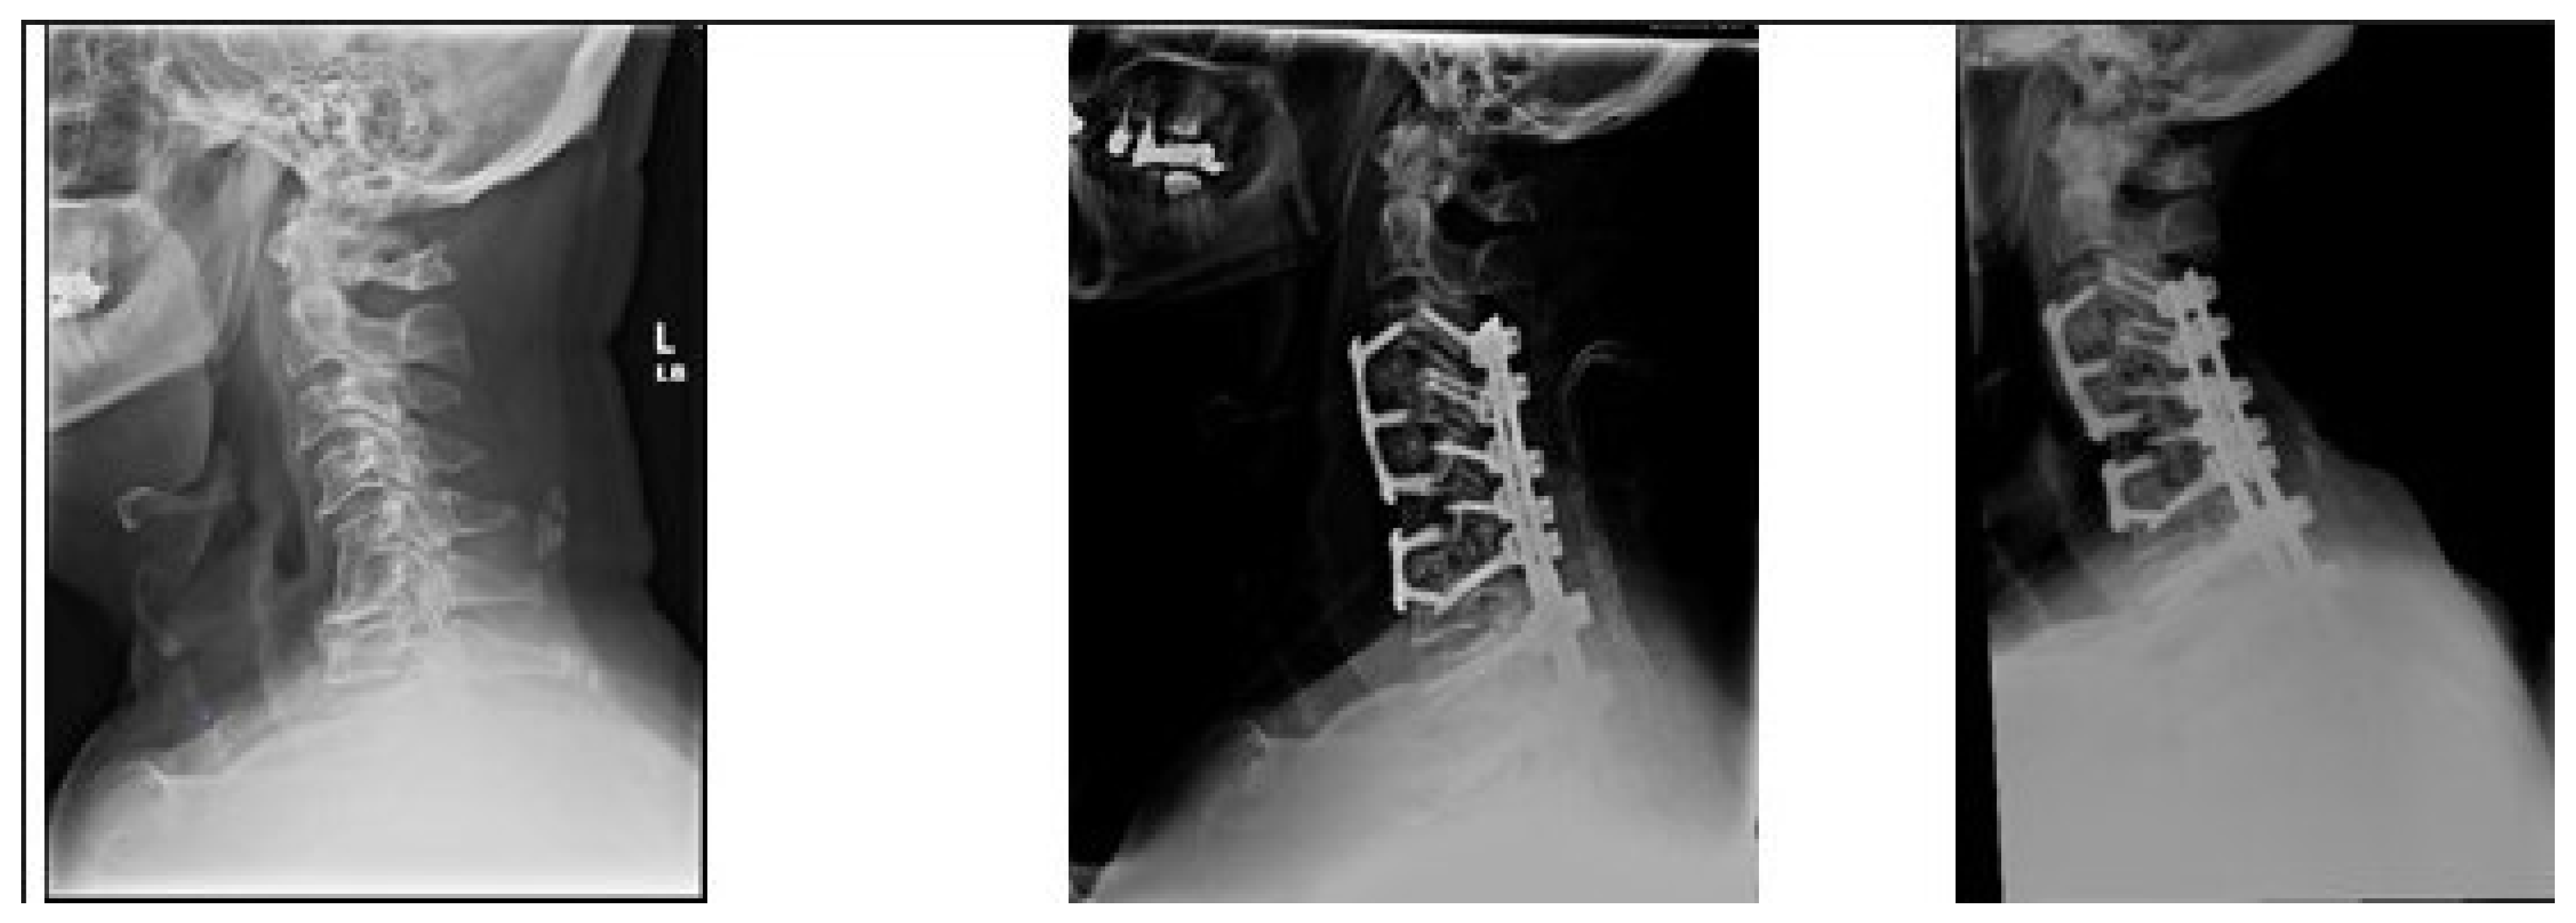

2. Methods

3.3. Postoperative Distal Junctional Kyphosis